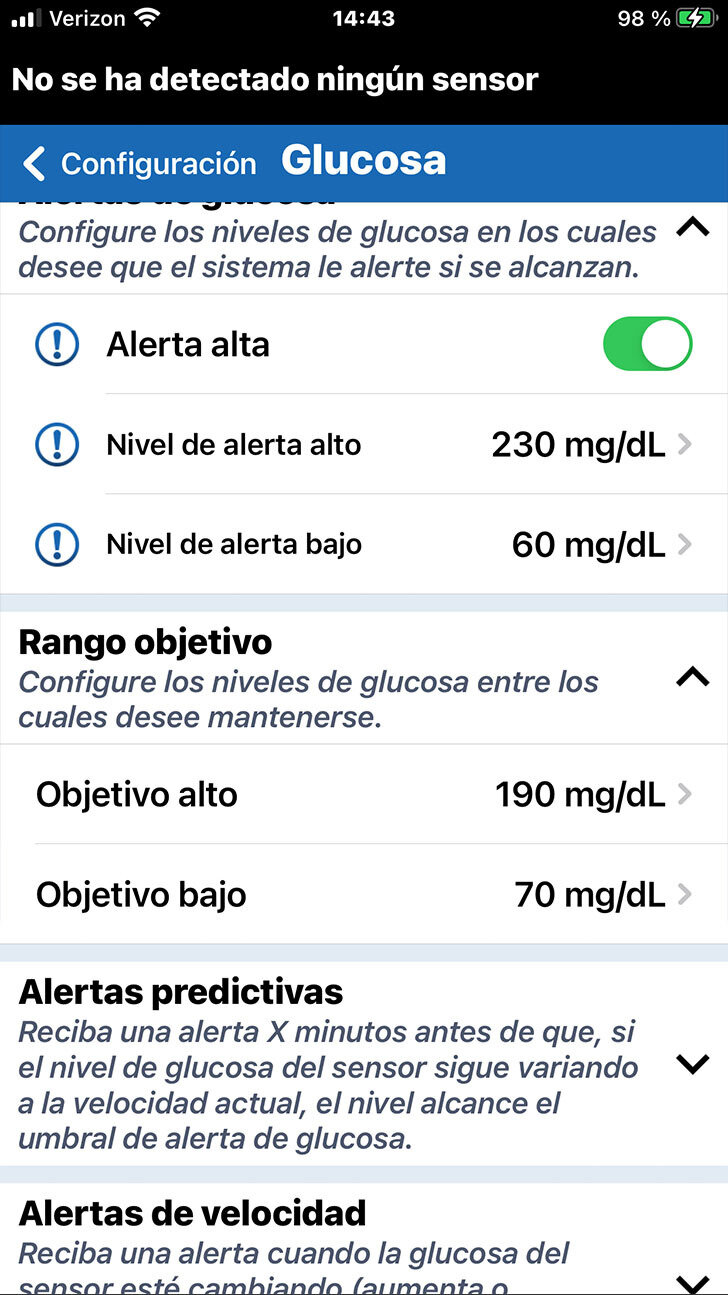

Debajo de Alertas de glucosa puede configurar su Intervalo objetivo de glucosa.

El intervalo objetivo de glucosa es la zona en la que tanto usted como el profesional de la salud deciden que deben estar sus niveles de glucosa la mayor parte del tiempo.

PERSONALICE LOS OBJETIVOS DE GLUCOSA

PERSONALICE LOS OBJETIVOS DE GLUCOSA

Nuevamente, solo tiene que tocar en el ajuste que le gustaría modificar, desplazarse hasta al valor deseado y, finalmente, tocar OK.

Debajo de Alertas de glucosa puede configurar su Intervalo objetivo de glucosa.

El intervalo objetivo de glucosa es la zona en la que tanto usted como el profesional de la salud deciden que deben estar sus niveles de glucosa la mayor parte del tiempo.

Tenga en cuenta que los niveles objetivo

de glucosa solo se pueden programar dentro de los niveles de alertas

de glucosa que ha definido.

PERSONALICE LOS OBJETIVOS DE GLUCOSA

Nuevamente, solo tiene que tocar en el ajuste que le gustaría modificar, desplazarse hasta al valor deseado y, finalmente, tocar OK.

Debajo de Alertas de glucosa puede configurar su Intervalo objetivo de glucosa.

El intervalo objetivo de glucosa es la zona en la que tanto usted como el profesional de la salud deciden que deben estar sus niveles de glucosa la mayor parte del tiempo.

En esta pantalla, también puede definir alertas predictivas y de velocidad de cambio.

Las alertas predictivas pueden

ser especialmente útiles para

los usuarios de la MCG.

No obstante, si es su primera vez con

la MCG, puede que lo mejor sea esperar para configurar estas alertas opcionales hasta que hable de estos ajustes con

su profesional de la salud.

Consulte la Guía del usuario para obtener más información.